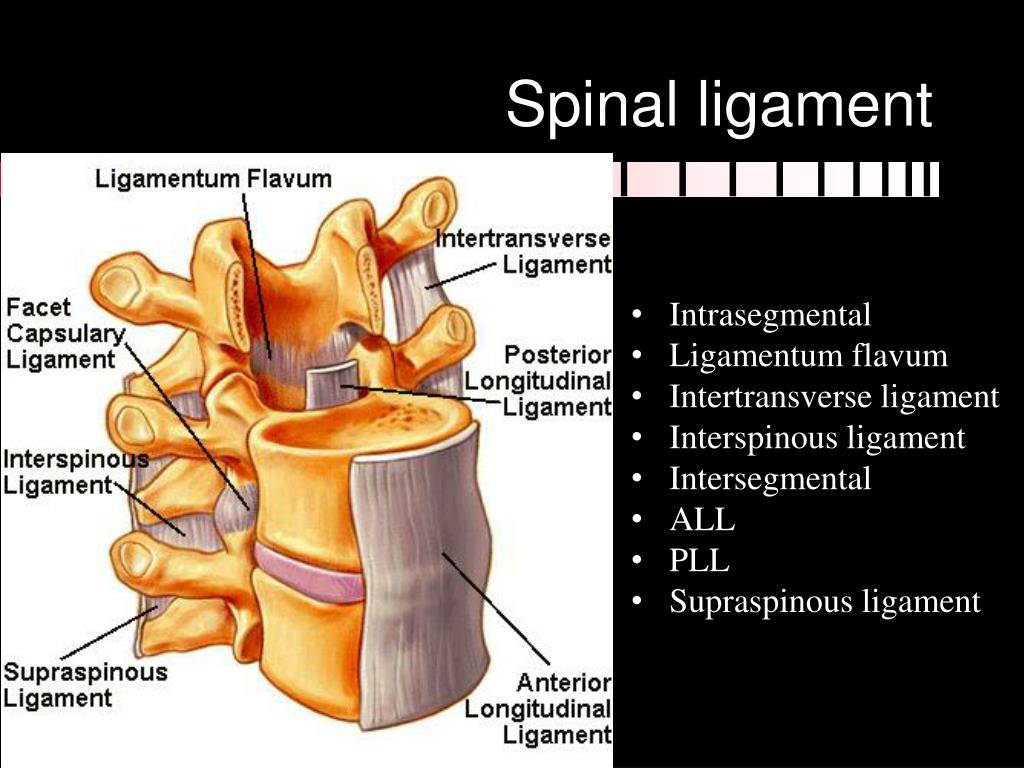

Pure Health - Anatomy 101 - Supraspinous ligament and interspinous ligament 📚 The supraspinous ligament and interspinous ligament work together to limit flexion of the spine by limiting separation of the spinous

DOCS - The interspinous ligament is located between the spinous processes of adjacent vertebrae in the spine. It extends from the base of one spinous process to the apex of the next,